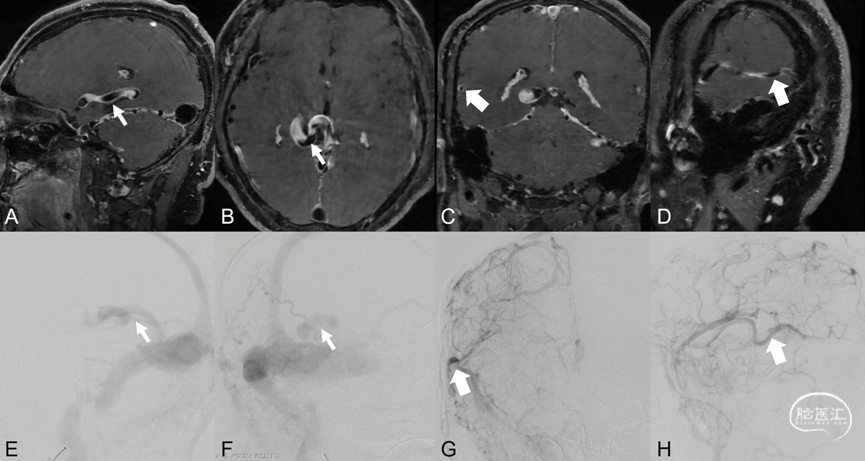

图5. CT平扫建左侧颞叶低密度影,脑回变浅,提示左侧颞叶肿胀,局部发生静脉性梗死 (A-D) ;左侧侧窦高密度 (C、D) ,提示静脉窦异常引流;CTA示左侧颞叶异常血管影,提示静脉引流瘀滞 (E-G),左侧横窦局部增宽及狭窄 (G、H) 。左侧颈外动脉造影证实左侧侧窦区硬脑膜动静脉瘘,左侧横窦狭窄,向对侧侧窦逆流,并向Labbe静脉逆流 (I、J) ;左侧颈内动脉造影示左侧大脑半球引流瘀滞,Labbe静脉不显影 (K、L) 。

图6. A-D弥散加权成像DWI显示左侧颞枕叶细胞毒性水肿;E-H T2WI成像显示左侧颞枕叶血管源性水肿;以上Labbe静脉相关脑区异常水肿征象提示同侧Labbe静脉引流异常。I、J左侧颈外动脉造影证实左侧侧窦区硬脑膜动静脉瘘,向Labbe静脉极其附属皮层静脉逆流;左侧颈内动脉造影示左侧Labbe静脉不显影,颞枕叶静脉引流瘀滞。